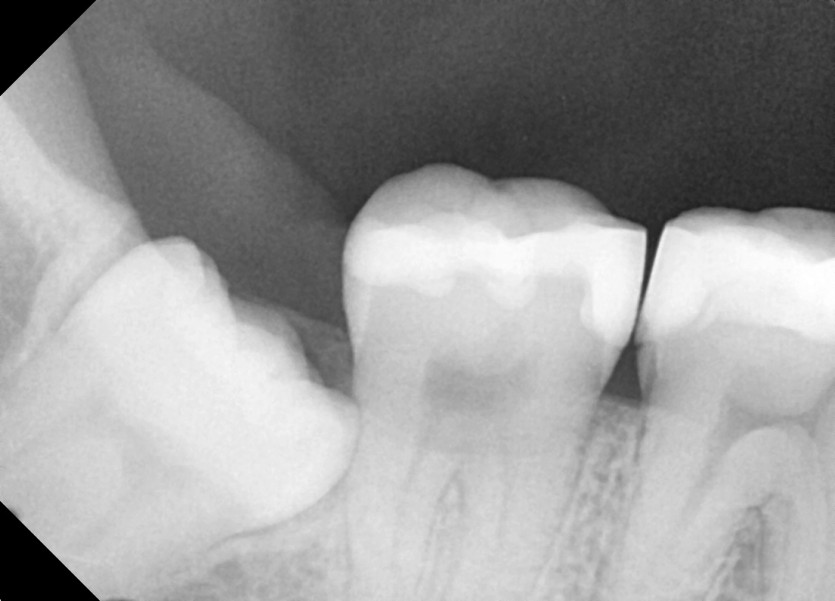

#38,48 사랑니 발치

구강 외과 전문의가 당일발치했습니다.